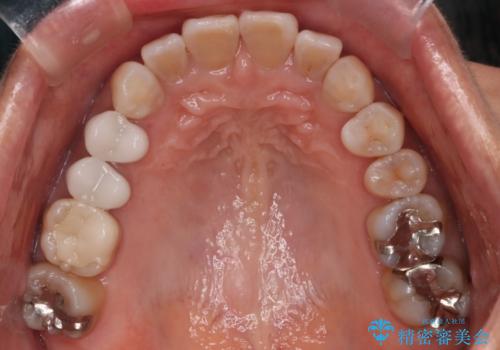

【インビザライン】下前歯だけを治したい

- 下前歯のがたつきにより唇を巻き込んでかんでしまい痛いため矯正をしたいという主訴で来院されました。今回は下顎前歯のみという強い希望があり、下顎のみのインビザライン矯正をしました。

叢生を改善するためのスペースはIPRと拡大を行いました。治療後は唇を巻き込んでしまう主訴が改善し、ご満足していただけました。